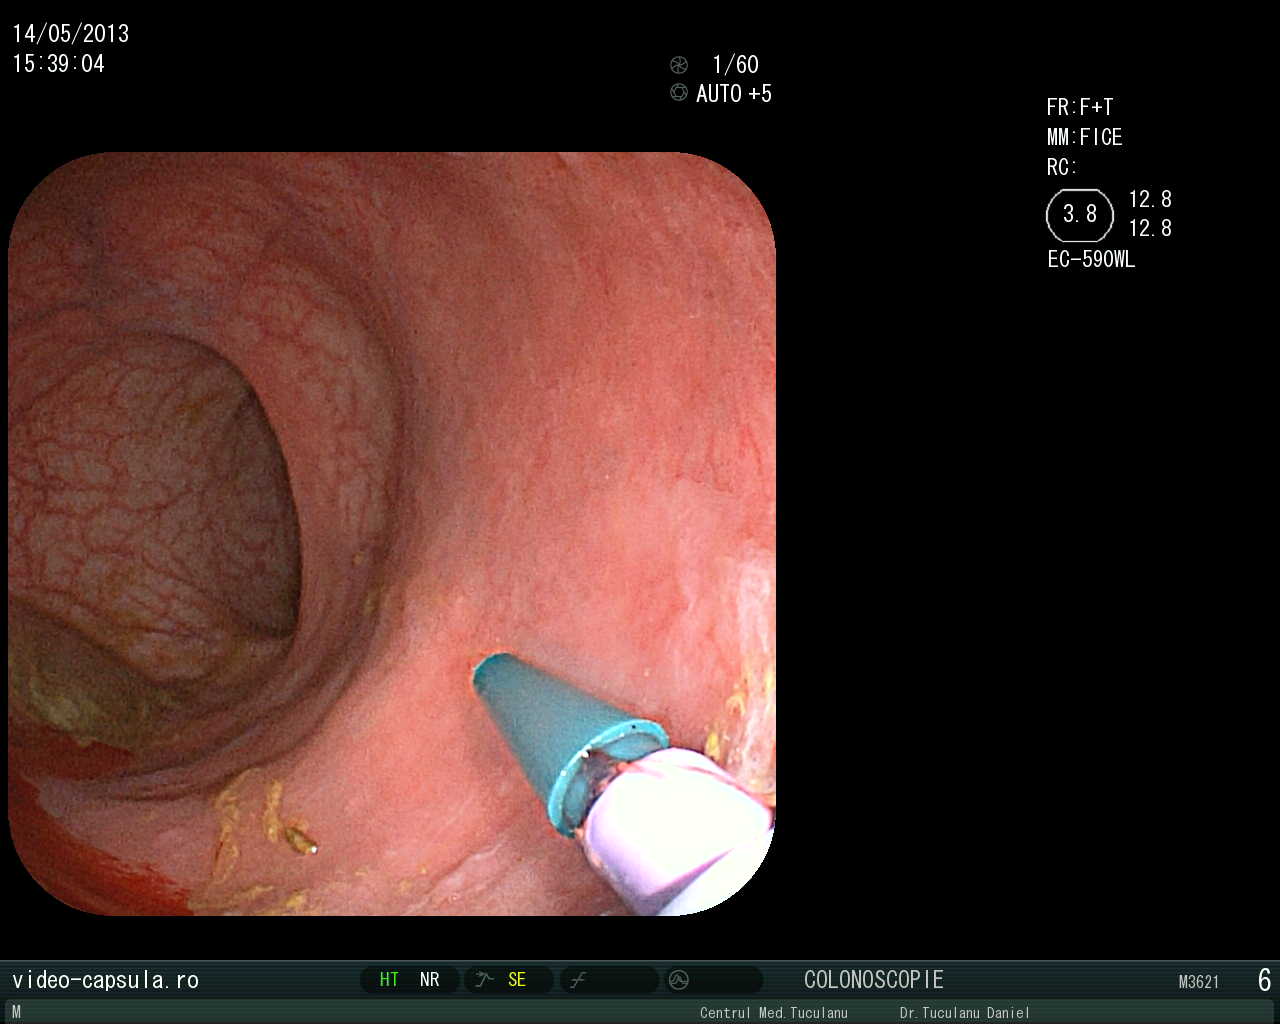

• Stent în cancer sigmoidian inoperabil •

Tratament endoscopic (nechirurgical) pentru evitarea operației paleative sau anusului contra naturii în cancerul colo-rectal avansat

Montarea de stent-uri (proteze) esofagiene, duodenale sau colo-rectale în stenoze canceroase sau necanceroase